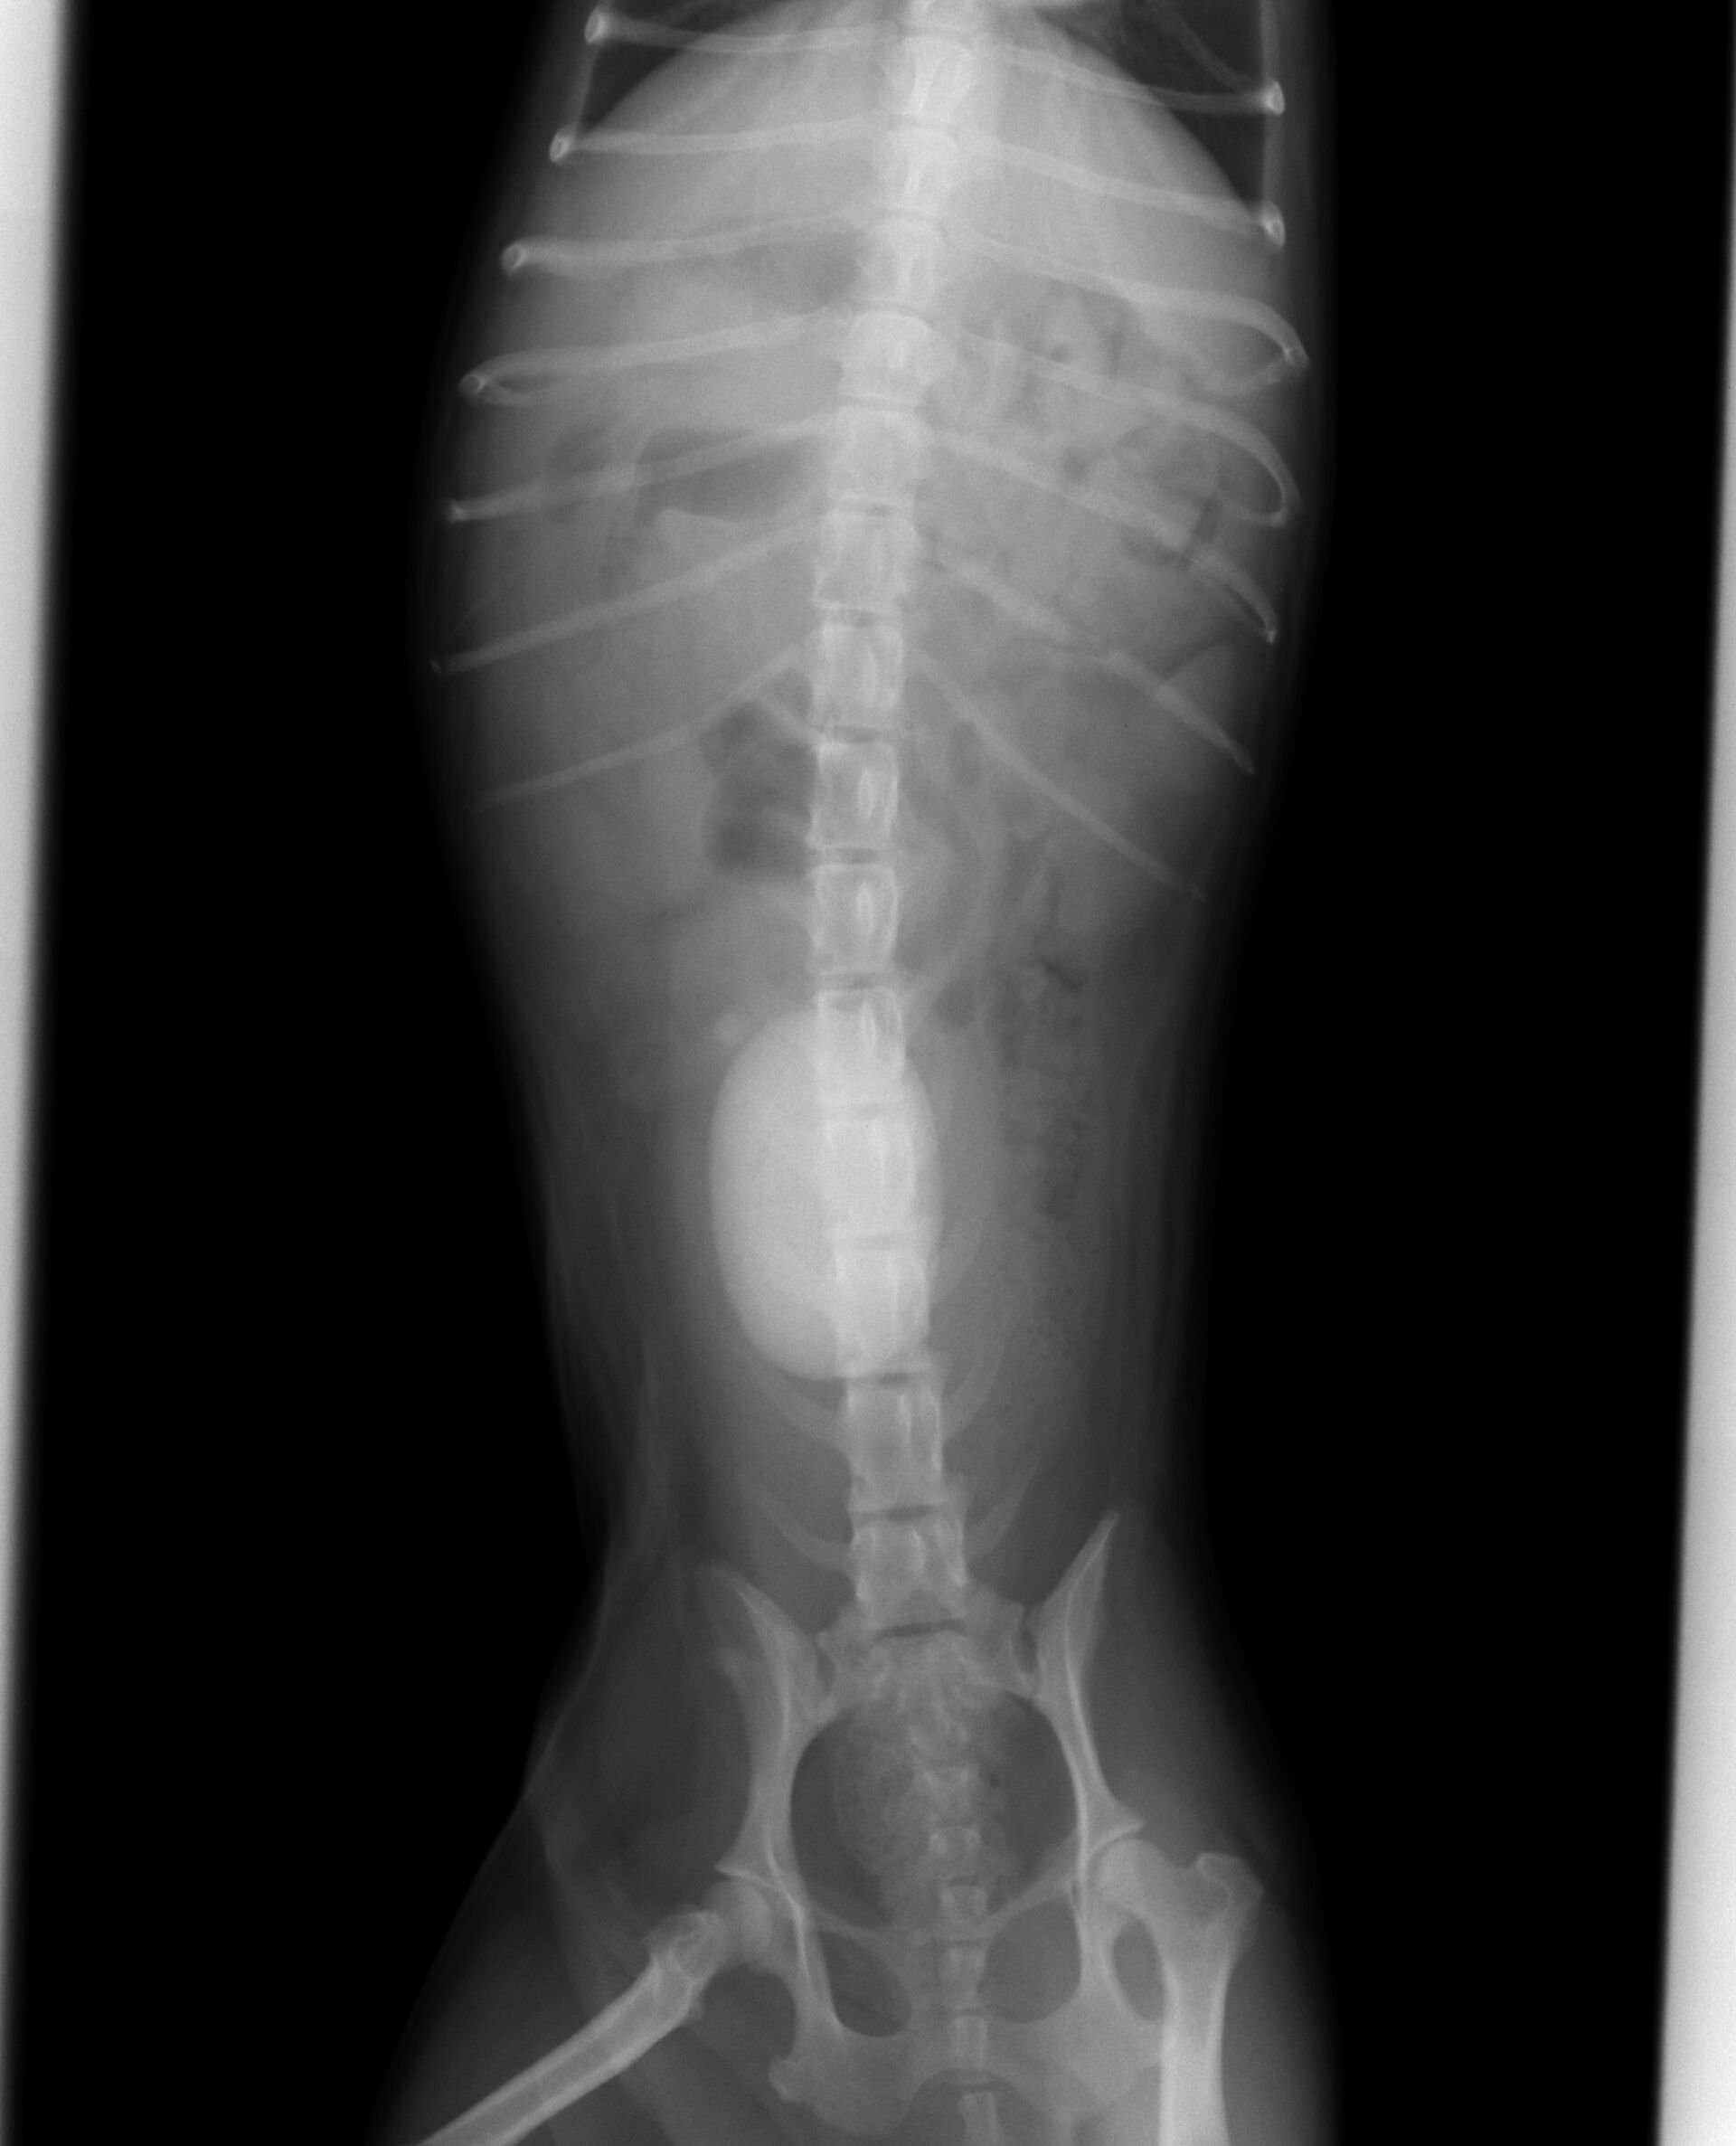

今回は膀胱結石です。

症例は7歳のシーズー(♀)です。

以前から血尿がずっと続いているということで来院されました。

下腹部を圧迫したところ、何か硬い大きな丸いものが手に触れたので、

膀胱結石に間違いないと判断し、レントゲンを撮りました。

それが下の写真です。かなり大きな膀胱結石が存在していました。

ここまで大きくなってしまうと膀胱切開して取り出すしかありません。